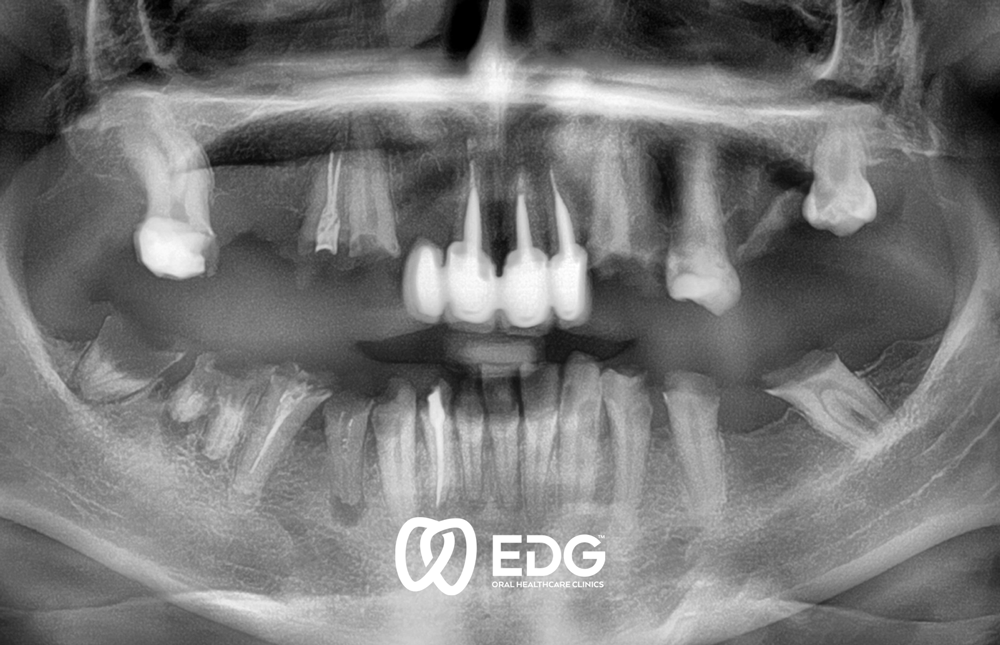

Η απώλεια ενός δοντιού μπορεί να οφείλεται σε διάφορους λόγους: τερηδόνα, περιοδοντίτιδα ή τραυματισμοί και ατυχήματα. Στην Κλινική Διεύθυνση Προσθετικής, προσφέρουμε στους ασθενείς μας ενημερωμένη περίθαλψη, η οποία γίνεται σύμφωνα με τα αισθητικά και λειτουργικά πρότυπα και τις ατομικές απαιτήσεις. Επιμένουμε στην αδιαχώριστη σύνδεση μεταξύ της μορφής και της λειτουργίας των οδοντικών προσθετικών. Μόνο η λειτουργικά καλή εργασία οδηγεί σε καλά αισθητικά αποτελέσματα. Για την επιλογή και την κατασκευή της οδοντικής πρόσθεσης, αντικειμενικά κριτήρια διαδραματίζουν ρόλο καθώς και ο τύπος και η ηλικία του ασθενούς. Η πολύπλοκη προσθετική ανασυγκρότηση της οδοντοστοιχίας απαιτεί ακριβή και εκτεταμένη διάγνωση προτού ξεκινήσουν τα επανορθωτικά μέτρα. Για να γίνει αυτό, απαιτείται μια ενδελεχής ιατρική αναισθησία, καθώς και η ραδιοδιαγνωστική και η χρήση σύγχρονων μεθόδων για τον ακριβή προσδιορισμό της θέσης των δοντιών και της κίνησης της κροταφογναθικής άρθρωσης. Για την προσθετική αποκατάσταση, χρησιμοποιούμε σύγχρονη τεχνολογία στεφάνης και γέφυρας, μερικές φορές και πλήρεις προθέσεις και εμφυτεύματα.